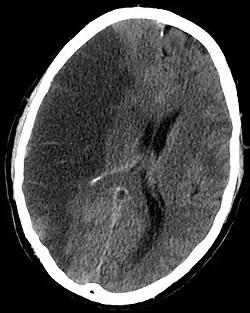

CT scan slice of the brain showing a right-hemispheric ischemic stroke (left side of image).

A stroke can be caused by a few different situations, but the basic result is the same. Blood flow to a section of the brain is stopped, which results in rapid depletion of oxygen and other nutrients in the starved section. The starved section of brain tissue quickly begins to die, and results in a lesion in the brain. The resulting lesion can be traced loss of various cognitive functions depending on the location and area of damage.[5]